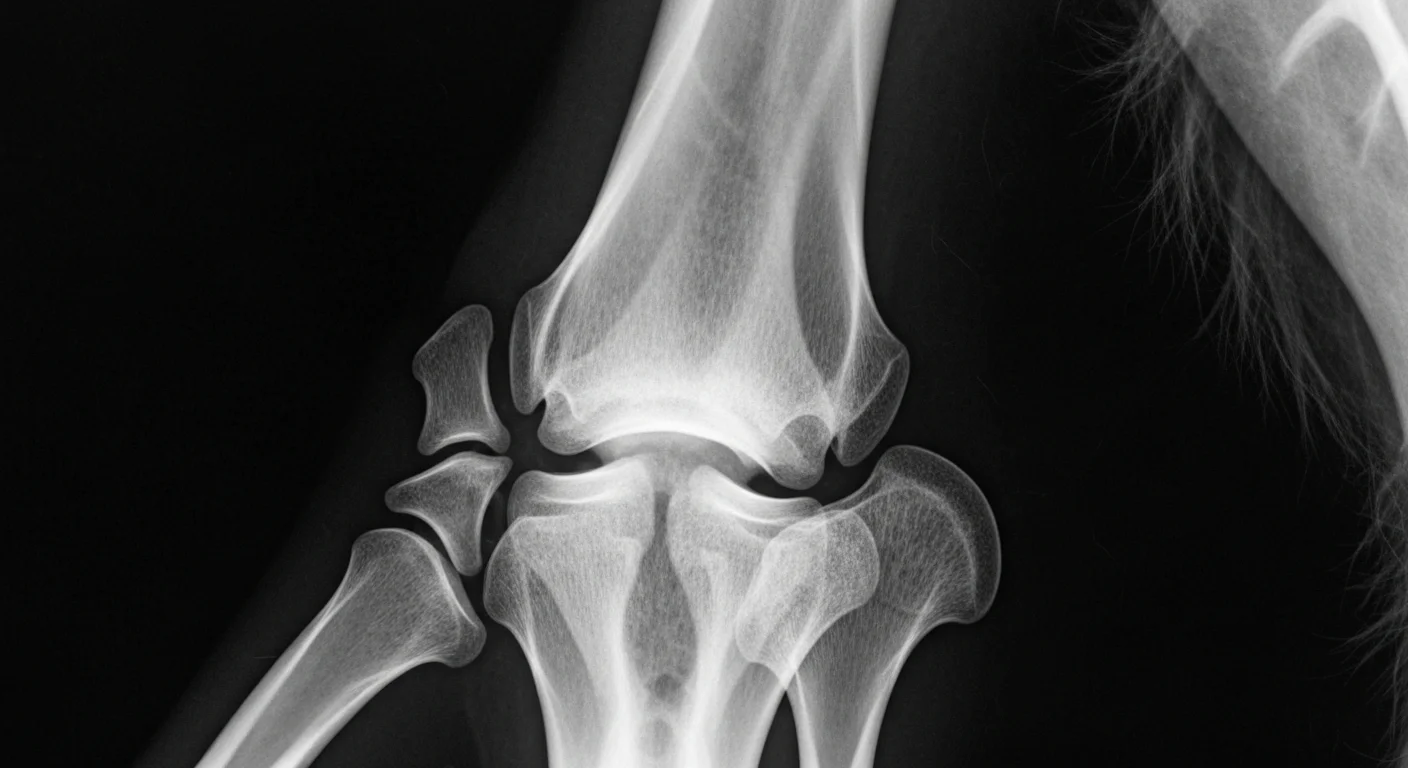

Radiograph showing characteristic elbow dysplasia changes in German Shepherd dog

Standard elbow screening protocol for German Shepherd Dogs follows the same radiographic positioning requirements as other breeds — mediolateral flexed and craniocaudal views of both elbows under standard protocol conditions. Breed-specific considerations include:

• UAP screening timing: Given the higher UAP prevalence, any GSD puppy showing forelimb lameness before 7 months should have UAP specifically excluded radiographically, as this is the primary surgical emergency in the breed's elbow disease spectrum. UAP that is diagnosed and operated before 5-6 months consistently achieves better outcomes than late diagnosis.

• Both elbows mandatory: The high bilateral rate in GSDs (approximately 45-50% for FCP; 40-45% for UAP) requires systematic bilateral evaluation. Any GSD with confirmed unilateral disease should have the contralateral elbow specifically evaluated by CT.